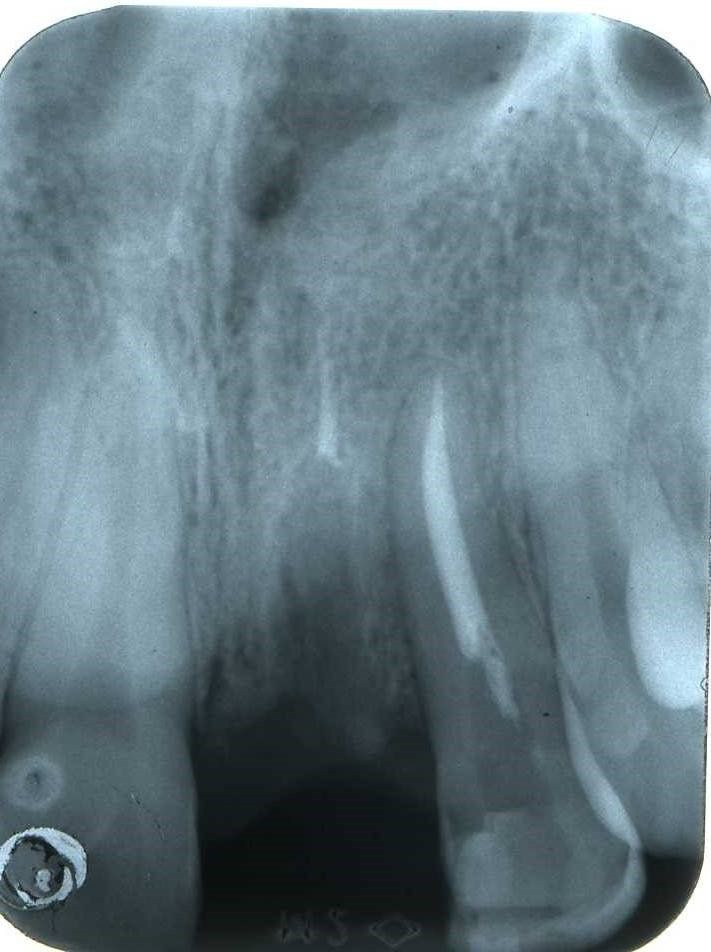

Immagini relative al mascellare superiore che rivelano sia la forma e l’entità dei volumi ossei residui sia l’areazione del seno mascellare

Un attento esame ed un seguente attento utilizzo chirurgico di questo seppur esiguo volume osseo residuo, possono consentire l’inserimento di due impianti che risolvono l’edentulia latero parziale superiore con l’applicazione successiva di tre elementi dentali. Infatti deve essere sottolineato che se il canino è presente in arcata due impianti sono sufficienti per sostenere i tre elementi protesici necessari al ripristino dei due premolari ed il primo molare necessari. Sono innumerevoli i pazienti trattati con successo presso questo studio nel corso degli ultimi trent’anni con questa tecnica ed i cui risultati sono stati pubblicati in un articolo del 2009.(3)